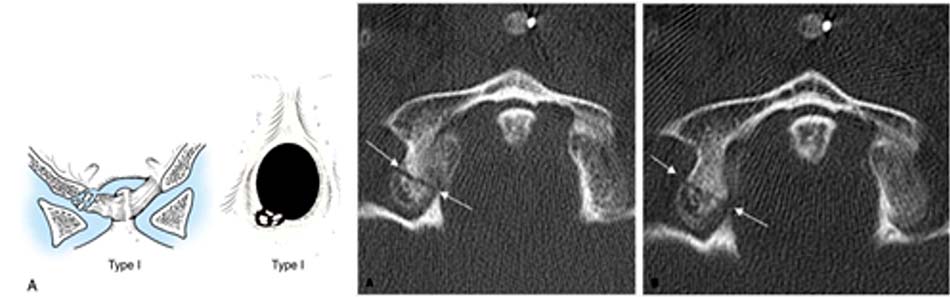

Với phẫu thuật vít qua cuống C2, một trong những vùng giải phẫu mà các phẫu thuật viên đặc biệt quan tâm là rãnh ĐMĐS ở C2. Các biến đổi giải phẫu ở vị trí này làm tăng nguy cơ tổn thương ĐMĐS và vít ra ngoài vỏ xương trong mổ. Vùng an toàn để đi vít nằm ở trên trong rãnh ĐMĐS, được xác định bằng khoảng cách từ bờ trong rãnh ĐMĐS đến ống sống (a), và khoảng cách từ bờ trên rãnh ĐMĐS đến diện khớp trên của C2 (e). Với ngưỡng cut-off là 4,5mm, có 4 typ giải phẫu rãnh ĐMĐS C2 (hình 1.10 và 1.11). Với typ II, vùng an toàn là rất hẹp, nguy cơ tổn thương ĐMĐS là rất cao khi vít qua cuống C2, ngay cả với vít 3,5mm [56].

Hình 1.24. Hình ảnh vỡ cung sau C1 đơn thuần (loại 1) - Loại II: gãy kết hợp một cung trước và một cung sau do lực ép thẳng trục phối hợp với nghiêng đầu. Thương tổn ít gặp nhất của vỡ C1. Hậu quả làm bửa một khối bên C1.

Hình 1.25. Hình ảnh vỡ cung sau C1 (loại 2) - Loại III: vỡ vụn C1 (gãy Jefferson). Tổn thương thường gặp sau gãy loại I, cơ chế do lực nén thẳng trục với tư thế đầu trung gian, tổn thương gãy 2 điểm cung trước và 1 hoặc 2 điểm ở cung sau.

Hình 1.26. Hình ảnh vỡ vụn C1 – gãy Jefferson (loại 3)